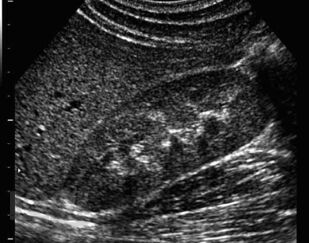

В основу монографии положены результаты собственных исследований и практический опыт авторов, использования ультразвуковых методов исследования мочевыделительной системы у тяжелой группы пациентов в промежуточном и позднем периодах позвоночно-спинальной травмы, проанализированы литературные данные отечественных и зарубежных авторов.

В монографии представлены современные методы комплексного ультразвукового исследования и патологические изменения мочевыделительной системы при позвоночно-спинальной травме. Описаны ультразвуковые симптомы поражения почек и верхних мочевых путей. Представлена разработанная авторами, эхосемиотика нейрогенного мочевого пузыря и эхосемиотика предстательной железы при позвоночно-спинальной травме. Описана технология проведения ультразвукового исследования у прикованных к постели и коляске, нуждающихся в постоянном постороннем уходе больных с последствиями позвоночно-спинальной травмы. Динамическое комплексное ультразвуковое исследование мочевыделительной системы позволяет осуществлять диагностику, мониторинг лечения и оценивать своевременность и эффективность урологического пособия пациентам, перенесшим позвоночно-спинальную травму.